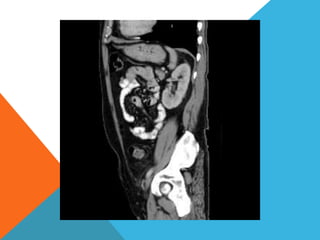

El paciente presentó síntomas de sangrado digestivo y pérdida de peso. Exámenes revelaron gastritis crónica asociada a H. pylori. Un tumor fue descubierto en una colonoscopia normal. La cirugía removió un tumor fibroide solitario, una rara neoplasia mesenquimal que usualmente crece lento y tiene bajo potencial de malignidad. El pronóstico después de la remoción quirúrgica es generalmente bueno.